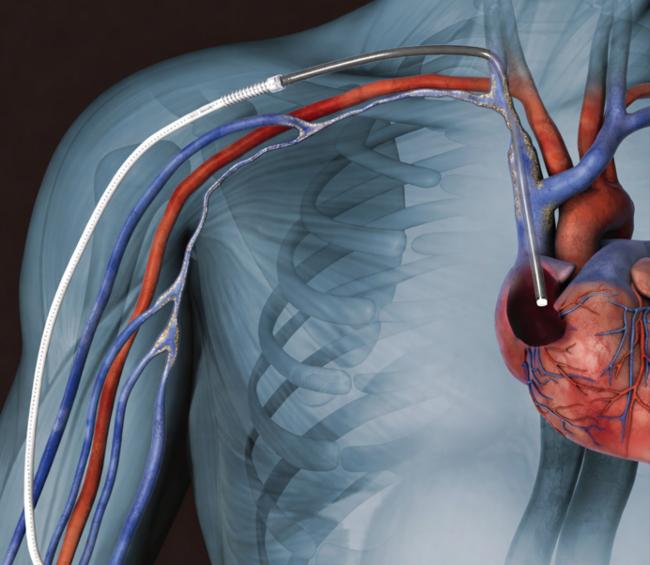

HeRO Graft는 협착된 중심정맥에 카테터(관)를 넣어서 심장과 직접 연결하고, 카테터와 연결한 인조혈관은 상완동맥과 연결해 투석 접근로를 형성한다. 이 제품은 한국의료기기안전정보원이 ‘희소·긴급도입 필요 의료기기’로 지정해 공급하고 있다.  송단(왼쪽) 순천향대 서울병원 외과, 김용재 영상의학과 교수

HeRO GRAFT 시술 모식도

HeRO GRAFT 시술 모식도